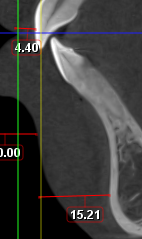

I played with my cbct a bit and this is something close to what I'm going to get.

4.4mm on maxilla and approx. 15mm on the lower

However, to pass all the convexities in a chad tier i would need 8.8mm on maxilla and 20mm on my lower jaw (likely 12/13mm lj + 8/7mm genio)